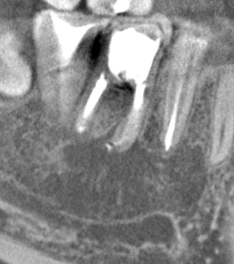

歯髄の焼灼、根管内外の感染組織や汚染物質の焼灼が行え、歯肉切除用のモードを選択することで、電気メスとしても使用可能です。

高周波通電により、チップ電極の先端部と接触した部位を発熱させることで、組織の焼灼・凝固・切開を行うことができます。

根管長測定機能によって根管内のチップ電極の位置を設定し、フットスイッチを踏むことで1秒間のHFCが行えます。